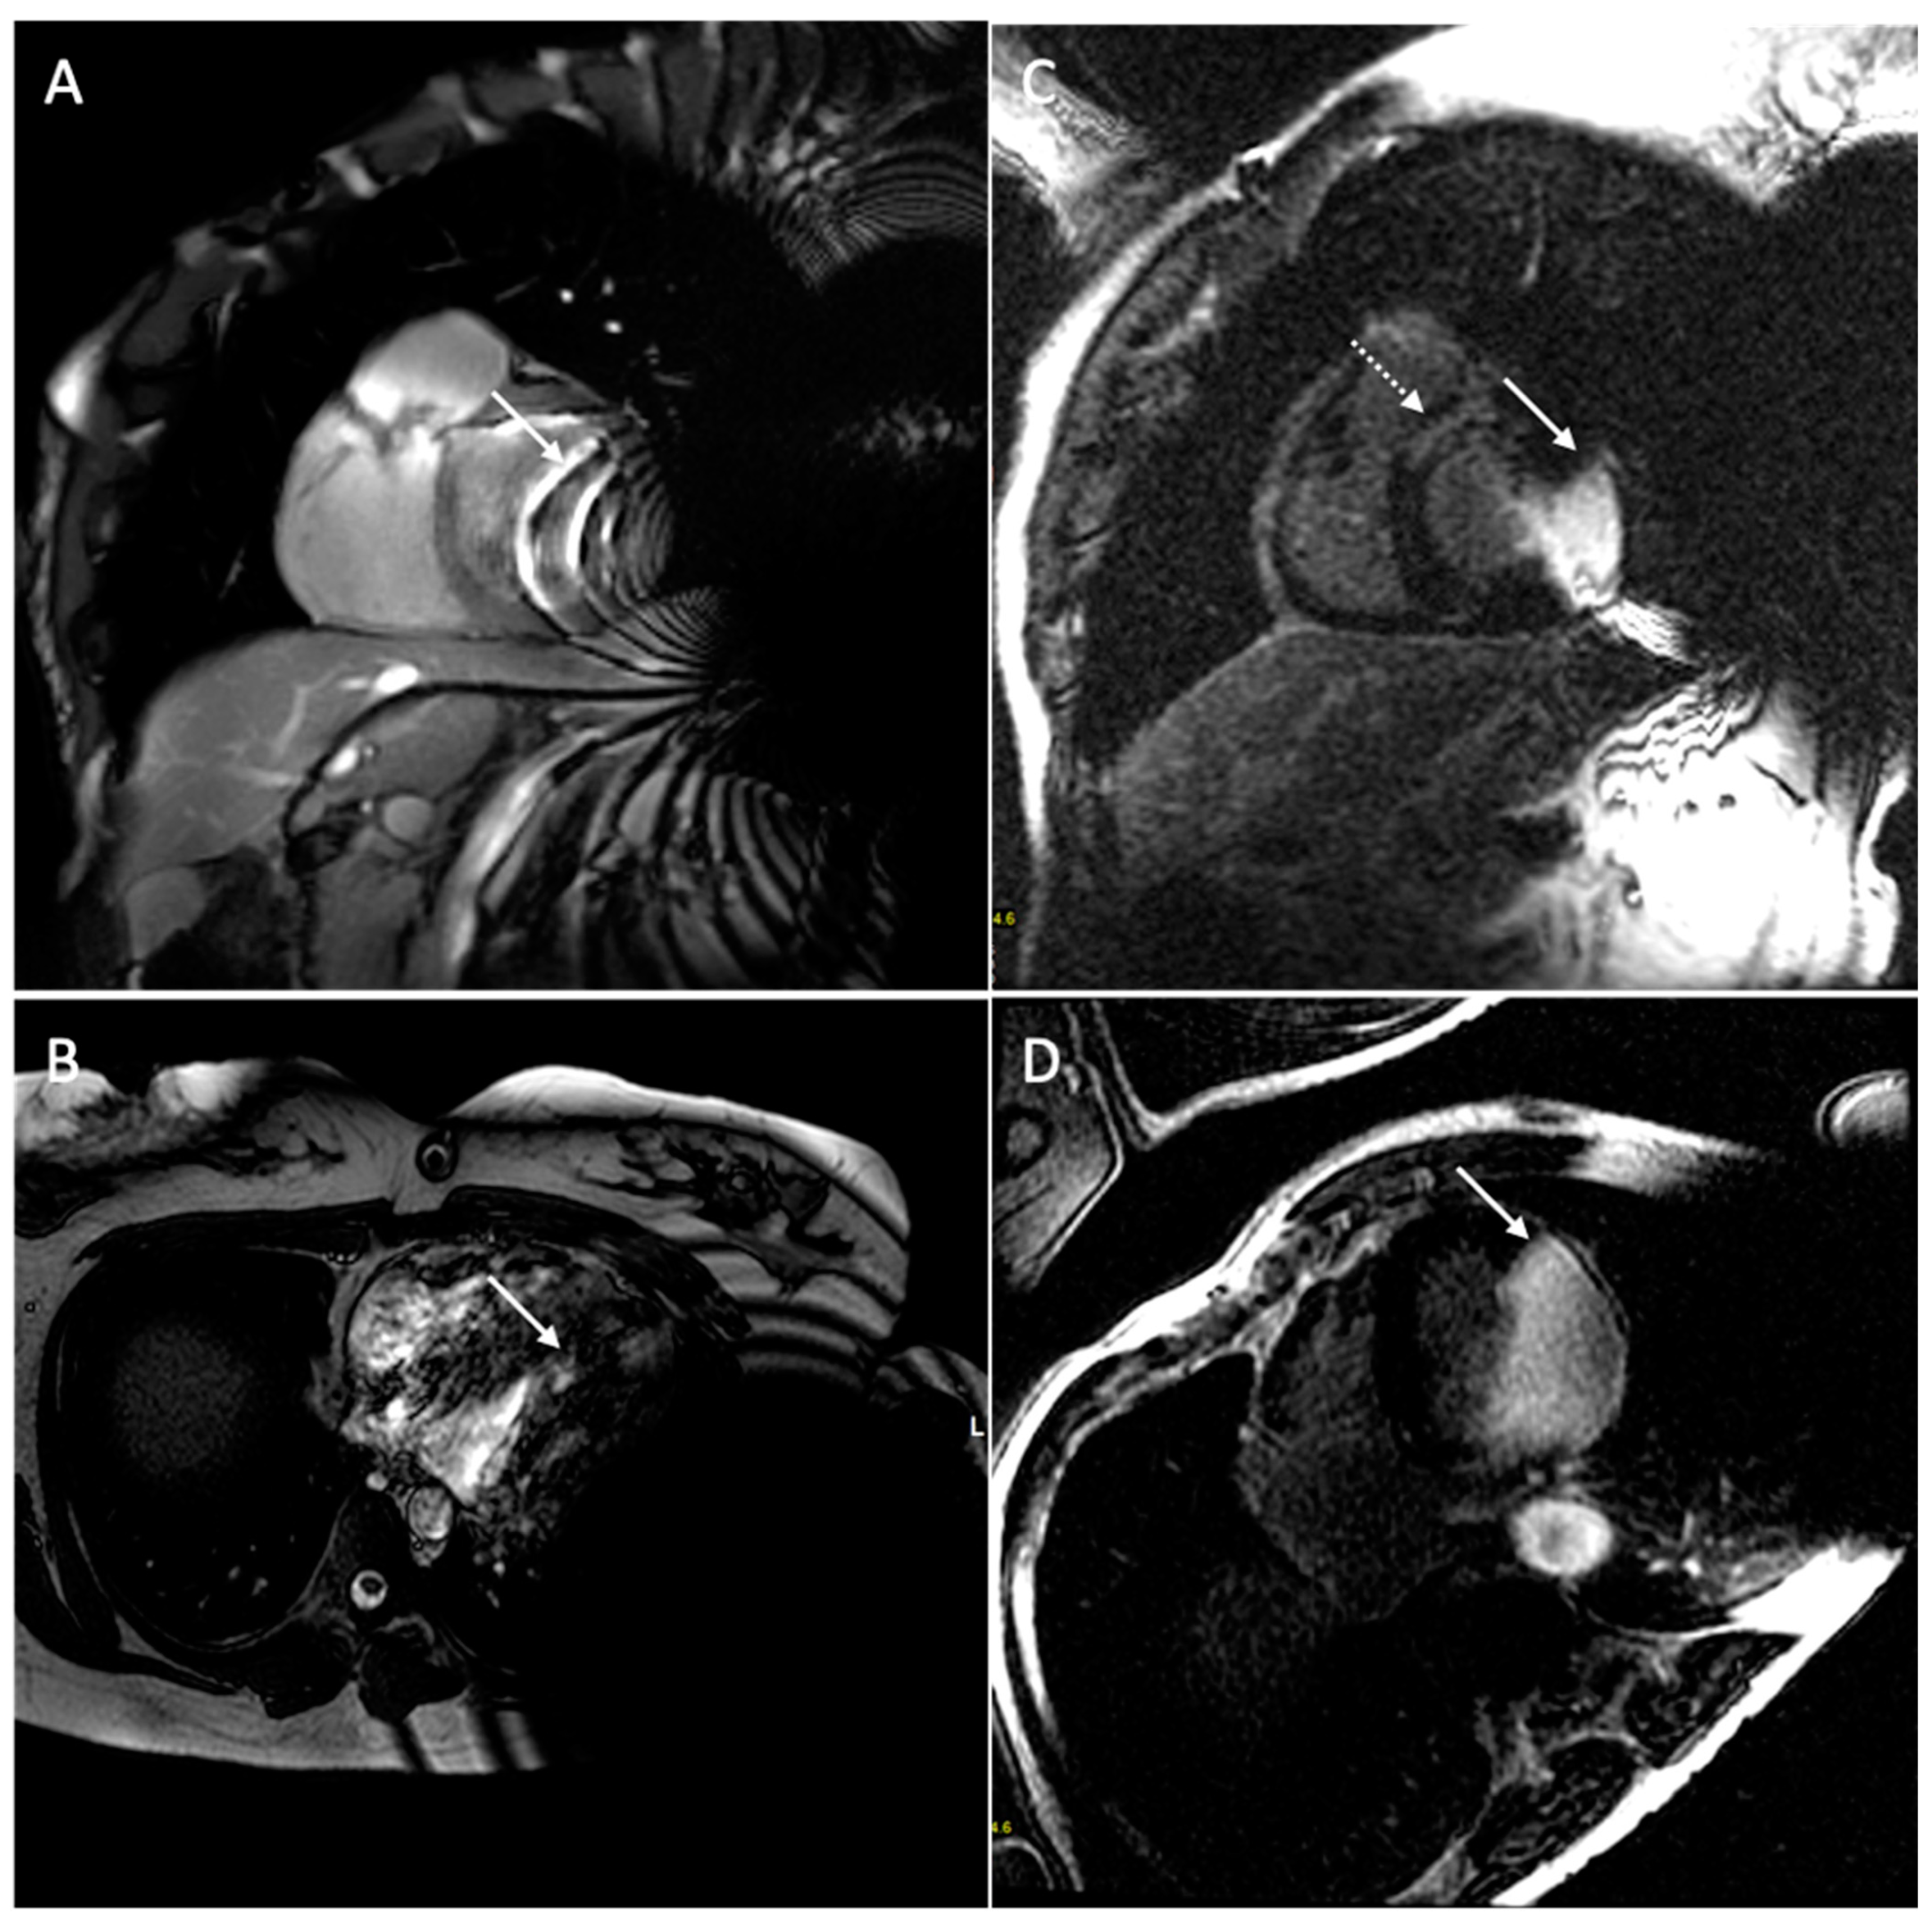

6. Issue: Artifact